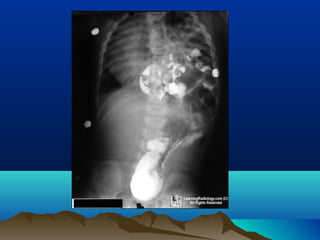

• An abdominal film showing

signs of small bowel

obstruction (multiple dilated

intestinal loops mainly in the

center of the abdomen with

vavulae coniventes)

• Erect film showing multiple

fluid levels in the small bowel